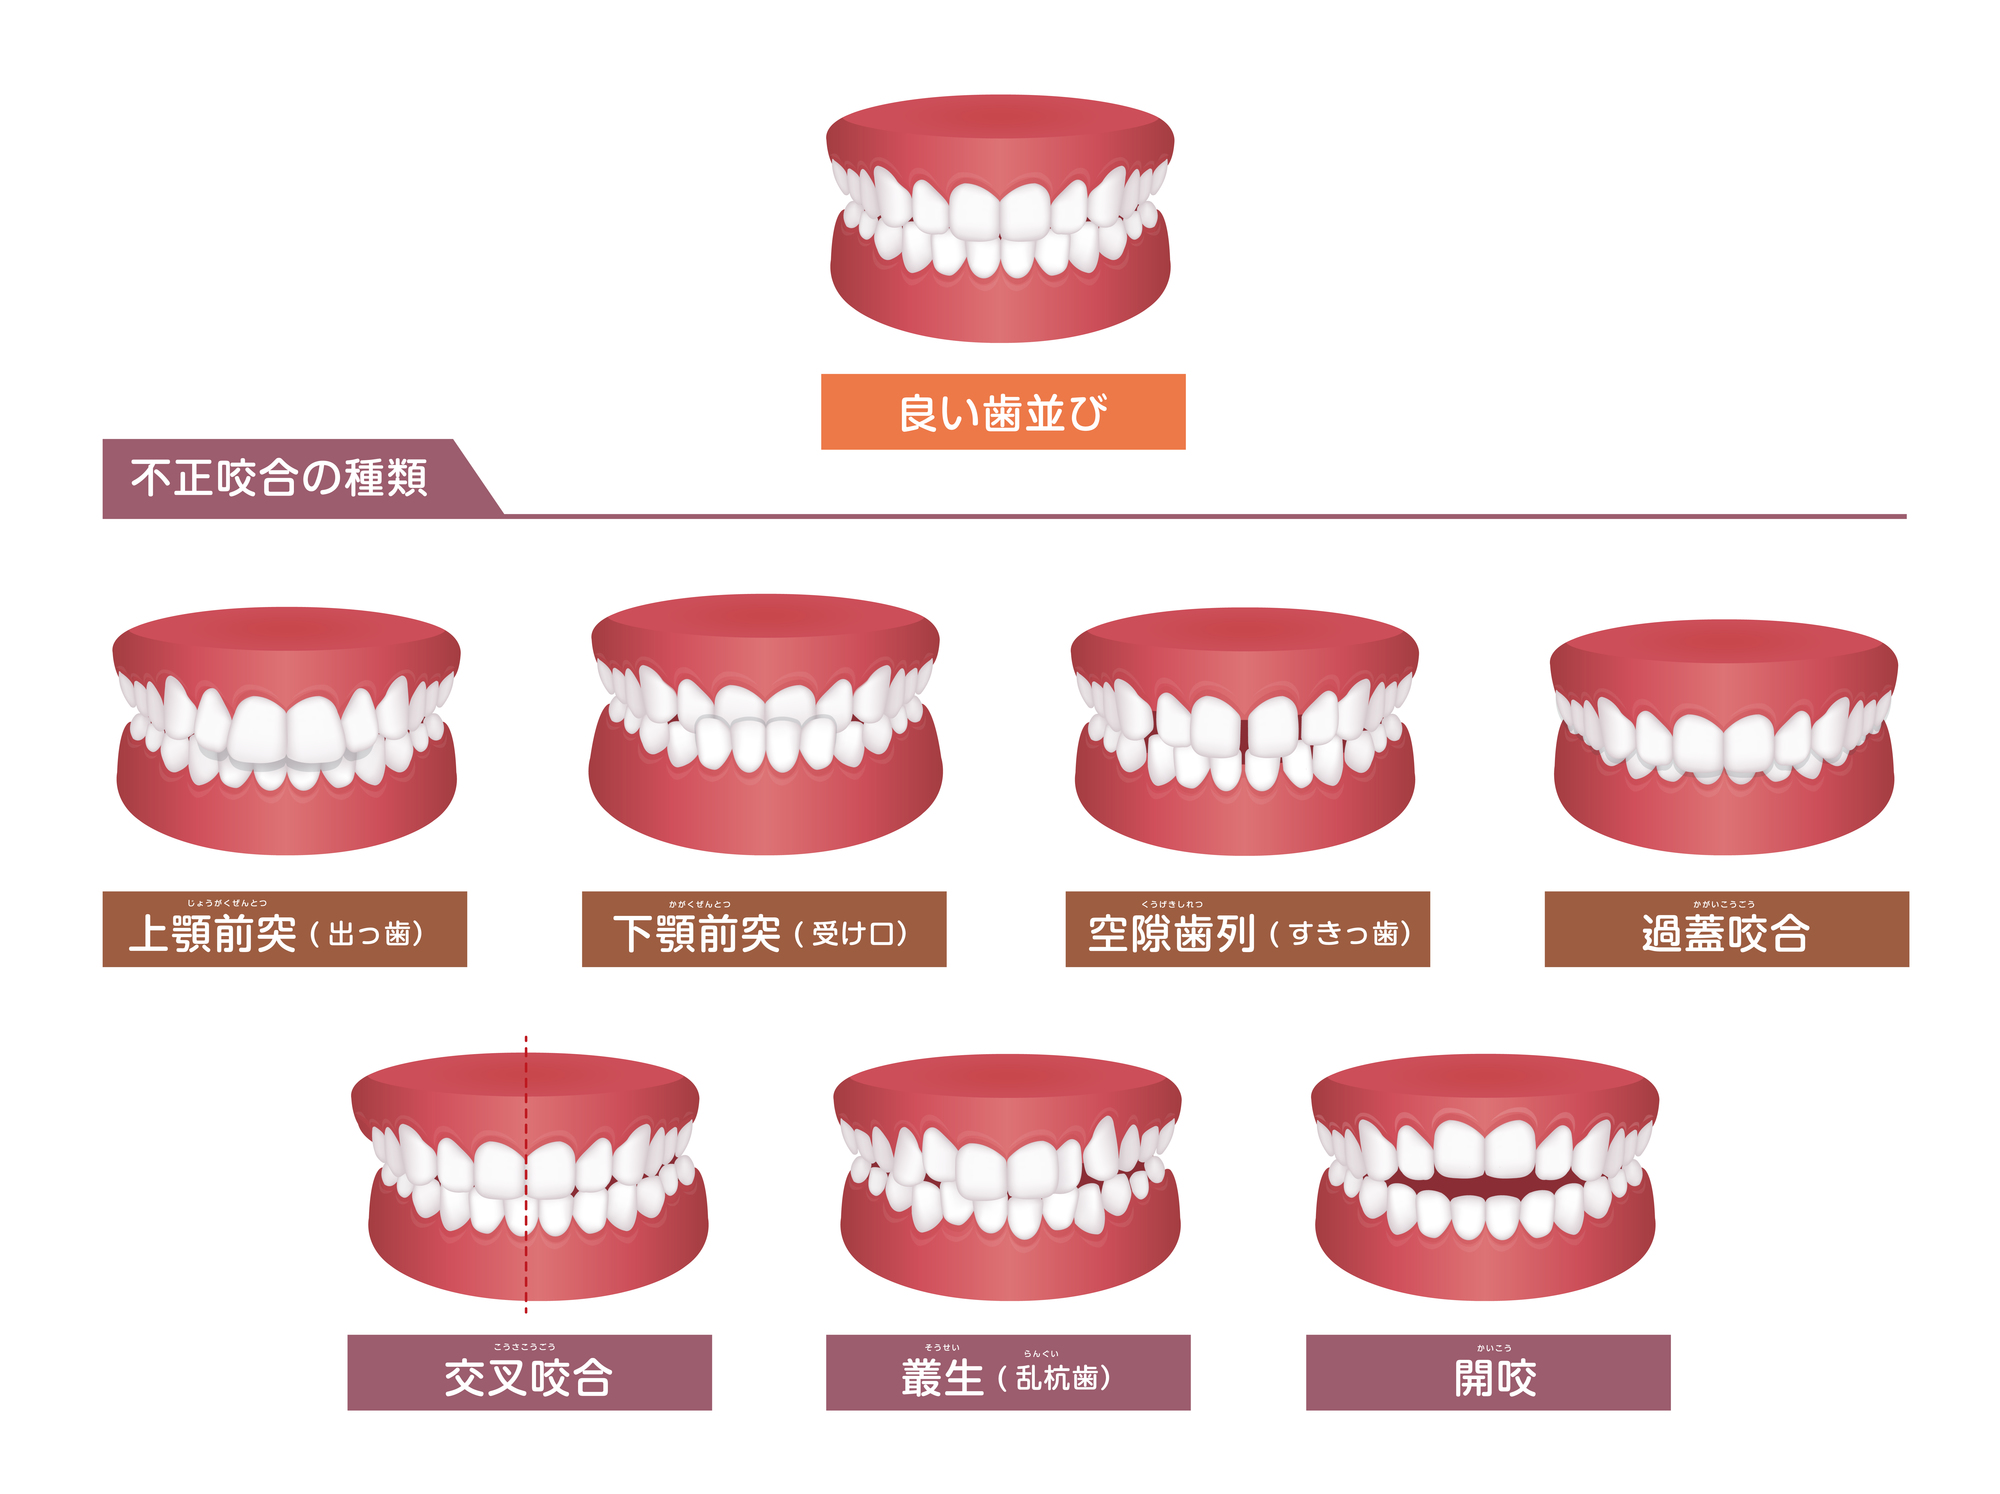

【診断】叢生・交叉咬合

上下の前歯にかなり叢生があり、特に右側(向かって左)2番の舌側転位と同じく右側の八重歯が目立っています。また2番が舌側に転位していることにより、上下の歯列の中心もずれてしまっています。

横から見ると上顎の前歯が唇側に傾斜しているのも分かりますね。

上下の歯列の中心のことを『正中』といい、叢生や咬み合わせに問題がある場合はこの正中にズレが生じることがあります。基本的には最終的に上下の正中ができるだけ一致するように治療計画を作成しますが、骨格に左右差があったり、上下の歯の本数が一致しないような場合は正中を完全に合わせるのは難しいです。

正中自体は多少ズレていても特に問題はないとされていますが、審美的な観点からできるだけ揃えたいという方も多くいらっしゃいます。